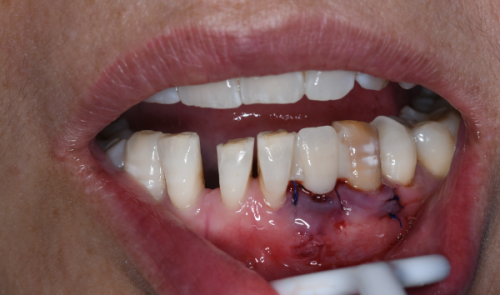

当你感觉种植牙有松动、疼痛,或者咀嚼时感觉和以前不一样,比如咬东西没力、有异常的声音等,这可能就是种植牙出现问题的信号。另外,如果发现人工牙冠有明显的磨损、变色,或者牙龈出现红肿、出血等情况,也需要及时去看医生,让医生判断是否需要更换种植牙。

定期去医院进行口腔检查也特别重要。医生可以通过专精的设备和检查方法,更正确地判断种植牙的状况。一般建议每半年到一年进行一次口腔检查,这样能及时发现问题并采取相应的措施。